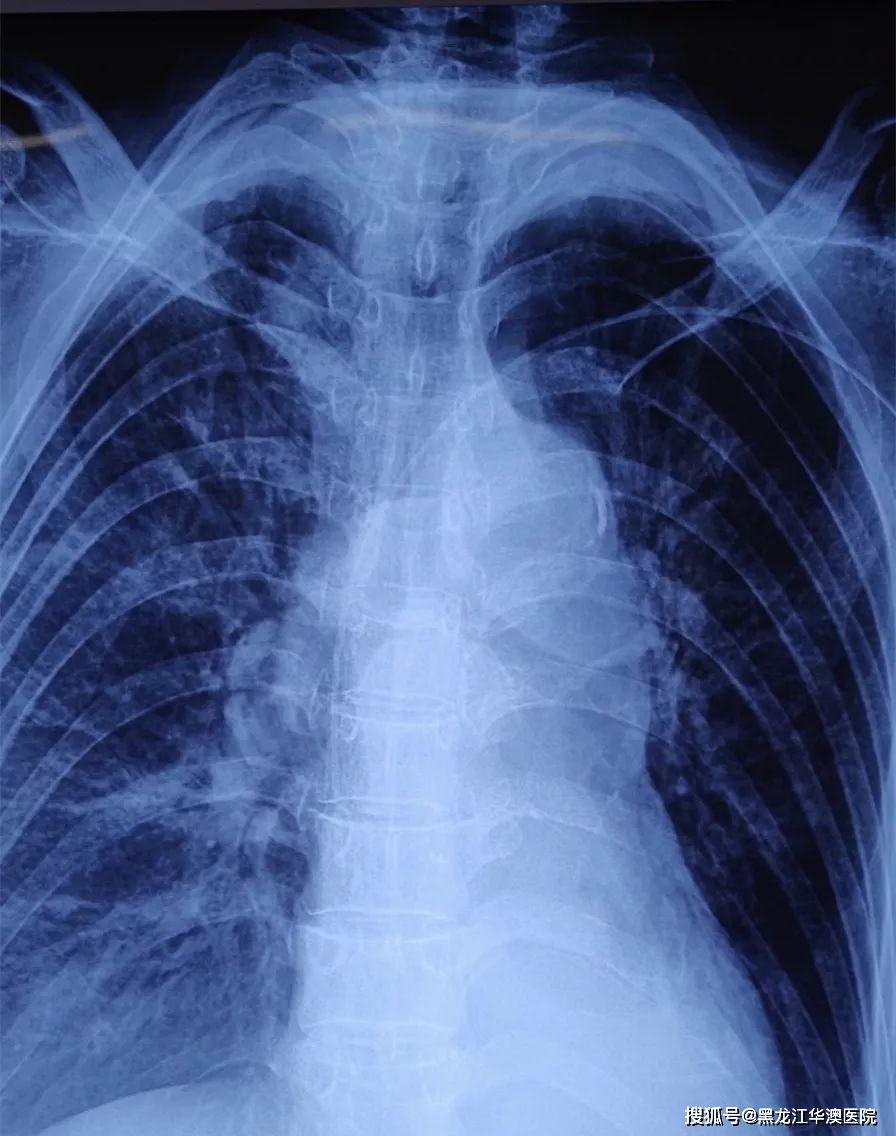

术后拍摄胸片,picc尖端定位良好.

胸部正位片验证picc_梁明柱